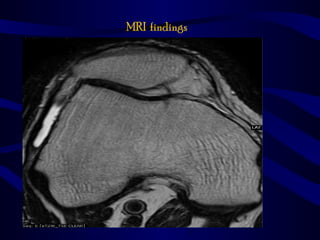

MRI findings